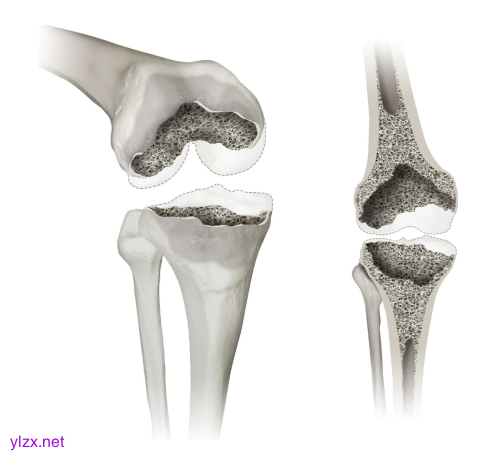

在3D斜视图(左)和正视图(右)中显示膝关节缺陷分类(KDC)的3型缺陷。虽然3型缺陷仍然存在松质骨耗竭,但与2型中的包含缺陷相比,干骺端的皮质缺陷被认为是不受控制的(超过周长的50%)